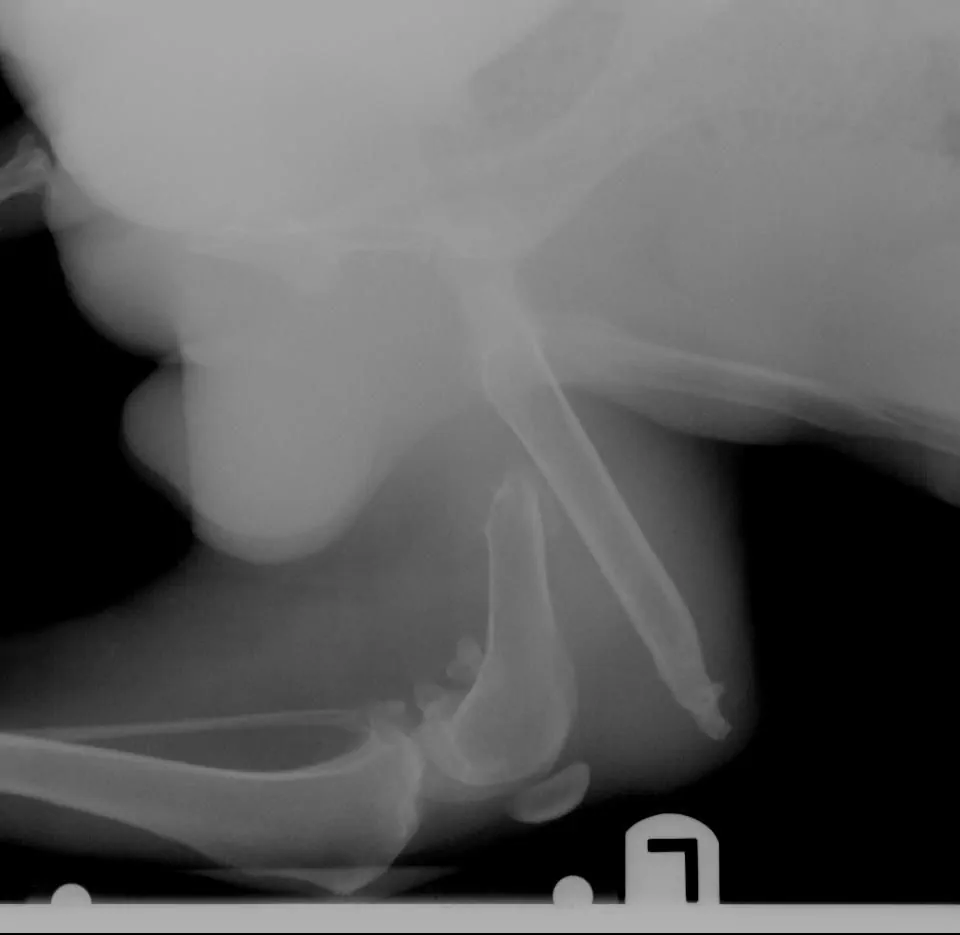

Nuestro querido amigo “Lu” ejemplifica un verdadero rescate. Él es un perro mestizo de mediana edad, oriundo de los páramos de Sigchos, que fue atropellado, no sabemos cuando, y se acostumbro a caminar con su pierna izquierda fracturada y a pesar de esta dificultad, era el guía de muchas personas que visitaban el sector en su camino al Quilotoa, en especial de los extranjeros que se enamoran de nuestra tierra, y fue así como una pareja de norteamericanos, dejaron que Lu entre en sus corazones.

Ellos decidieron buscar ayuda profesional para determinar que se podía hacer para aliviar su pierna fracturada. Al no disponer de mas tiempo dejaron a Lu al cuidado de personas que vigilan su recuperación en el país, pero su intención no fue abandonarlo, ya que Ashley y James han venido costeando los tratamientos de recuperación de Lu, así como los trámites de su viaje a EEUU para que pueda vivir con ellos. La historia es larga y hasta el momento apunta a un reencuentro feliz entre Ashley, James, Lu y su nueva hermana.